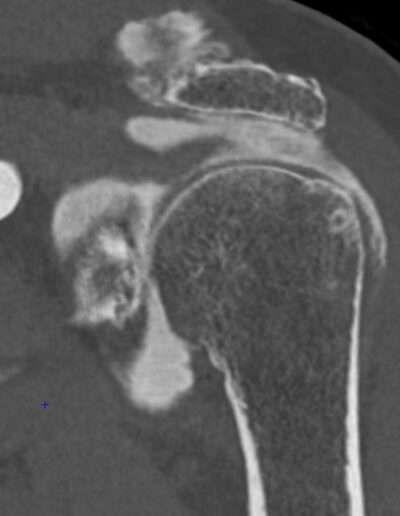

Shoulder Left

Patient 37 y/o, Male, right-handed

• 2005: Spontaneous episodes of subluxation – recurrence every year

• 01/2024: Posterior dislocation, reduced in ED